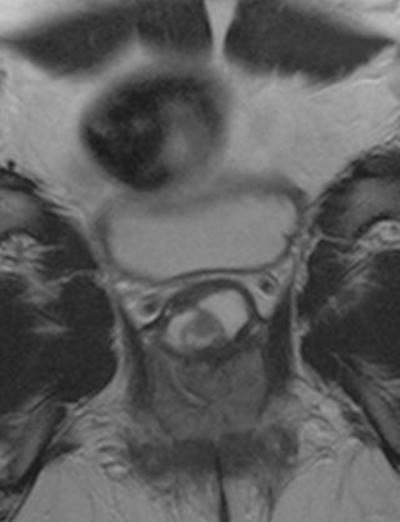

Fig. 13.1

Skene’s gland abscess

Prevention of Complications

Although most complications are treatable and reversible, the optimal scenario is to prevent or minimize potential for adverse outcomes. This process begins in the preoperative period, initiated during the diagnostic evaluation and work-up. The typical evaluation of patients with a suspected UD consists of a history, physical examination, cystourethroscopy, and appropriate imaging, including voiding cystourethrograpy and magnetic resonance imaging as clinically indicated. For patients with lower urinary tract symptoms or incontinence, videourodynamic studies may be utilized to evaluate for the presence of stress incontinence, voiding dysfunction, and specifically for the presence of a closed, competent bladder neck at rest. With the presence of stress incontinence or an incompetent bladder neck, patients can be offered concomitant placement of an autologous fascial sling at the time of UD excision. Urine cytology, when positive, can assist in making the correct diagnosis of malignancy; however, negative cytology cannot rule out malignancy. In all cases, UDs should be sent for permanent pathologic evaluation following excision to evaluate for malignant tissue. Preoperative urine cultures are obtained to appropriately tailor preoperative antibiotics and decrease the risks of intraoperative and postoperative infection. The differential diagnosis of periurethral masses (Table 13.1) is extensive and includes Skene’s gland abscess (Fig. 13.1), vaginal leiomyoma [2], and primary urethral cancer. Therefore, the importance of a correct diagnosis prior to undertaking surgical excision cannot be overemphasized.